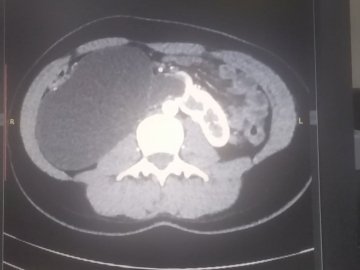

17-річна пацієнтка мала вроджену ваду сечовидільної системи - підковоподібну нирку (зрощення двох нирок). Стан її здоров’я погіршувався упродовж багатьох років, аж поки права половина підковоподібної нирки перестала функціонувати.

Лікарі діагностували термінальний гідронефроз із наслідками, гідронефротичну трансформацію правої половини підковоподібної нирки, вторинну артеріальну гіпертензію.